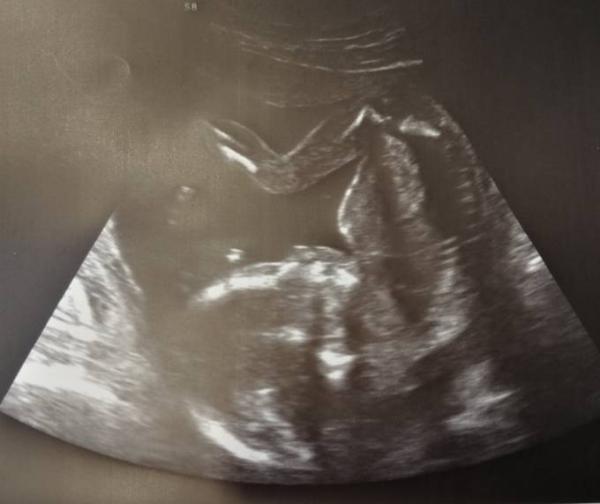

Hallo Mädels, Hatte gerade meinen zweiten großen Ultraschall Kerngesund mein kleiner Wonneproppen, Etwas größer als eigentlich sein sollte, aber noch im Rahmen 13,3 cm Gewicht 293 gramm. Das Problem mit der Frauenärztin ist auch geklärt ich hab ab Januar eine andere die aber alle Termine macht und die nach der Aussage meiner Ärztin sehr nett sein soll. Ansonsten ist auch alles prima entwickelt beim Kind und ich darf euch sagen, Wir sind Team ROSA juhuuu wir haben uns beide ein Mädchen gewünscht und es wird eins, wir freuen uns riesig und wir nennen sie Josephine, wenns so bleibt, sind ja noch ein paar Wochen bis dahin , ach ja und eine Hinterwandplazenta habe ich also es steht für eine natürliche Geburt nichts im Wege bisher. Toi Toi Toi, dass das auch so bleibt. Ich bin einfach nur glücklich gerade Am Ende gibt es noch ein schönes Bild, bei dem sie rumturnt ohne Ende

Bild zu Termin :) - Forum für April - Mamis